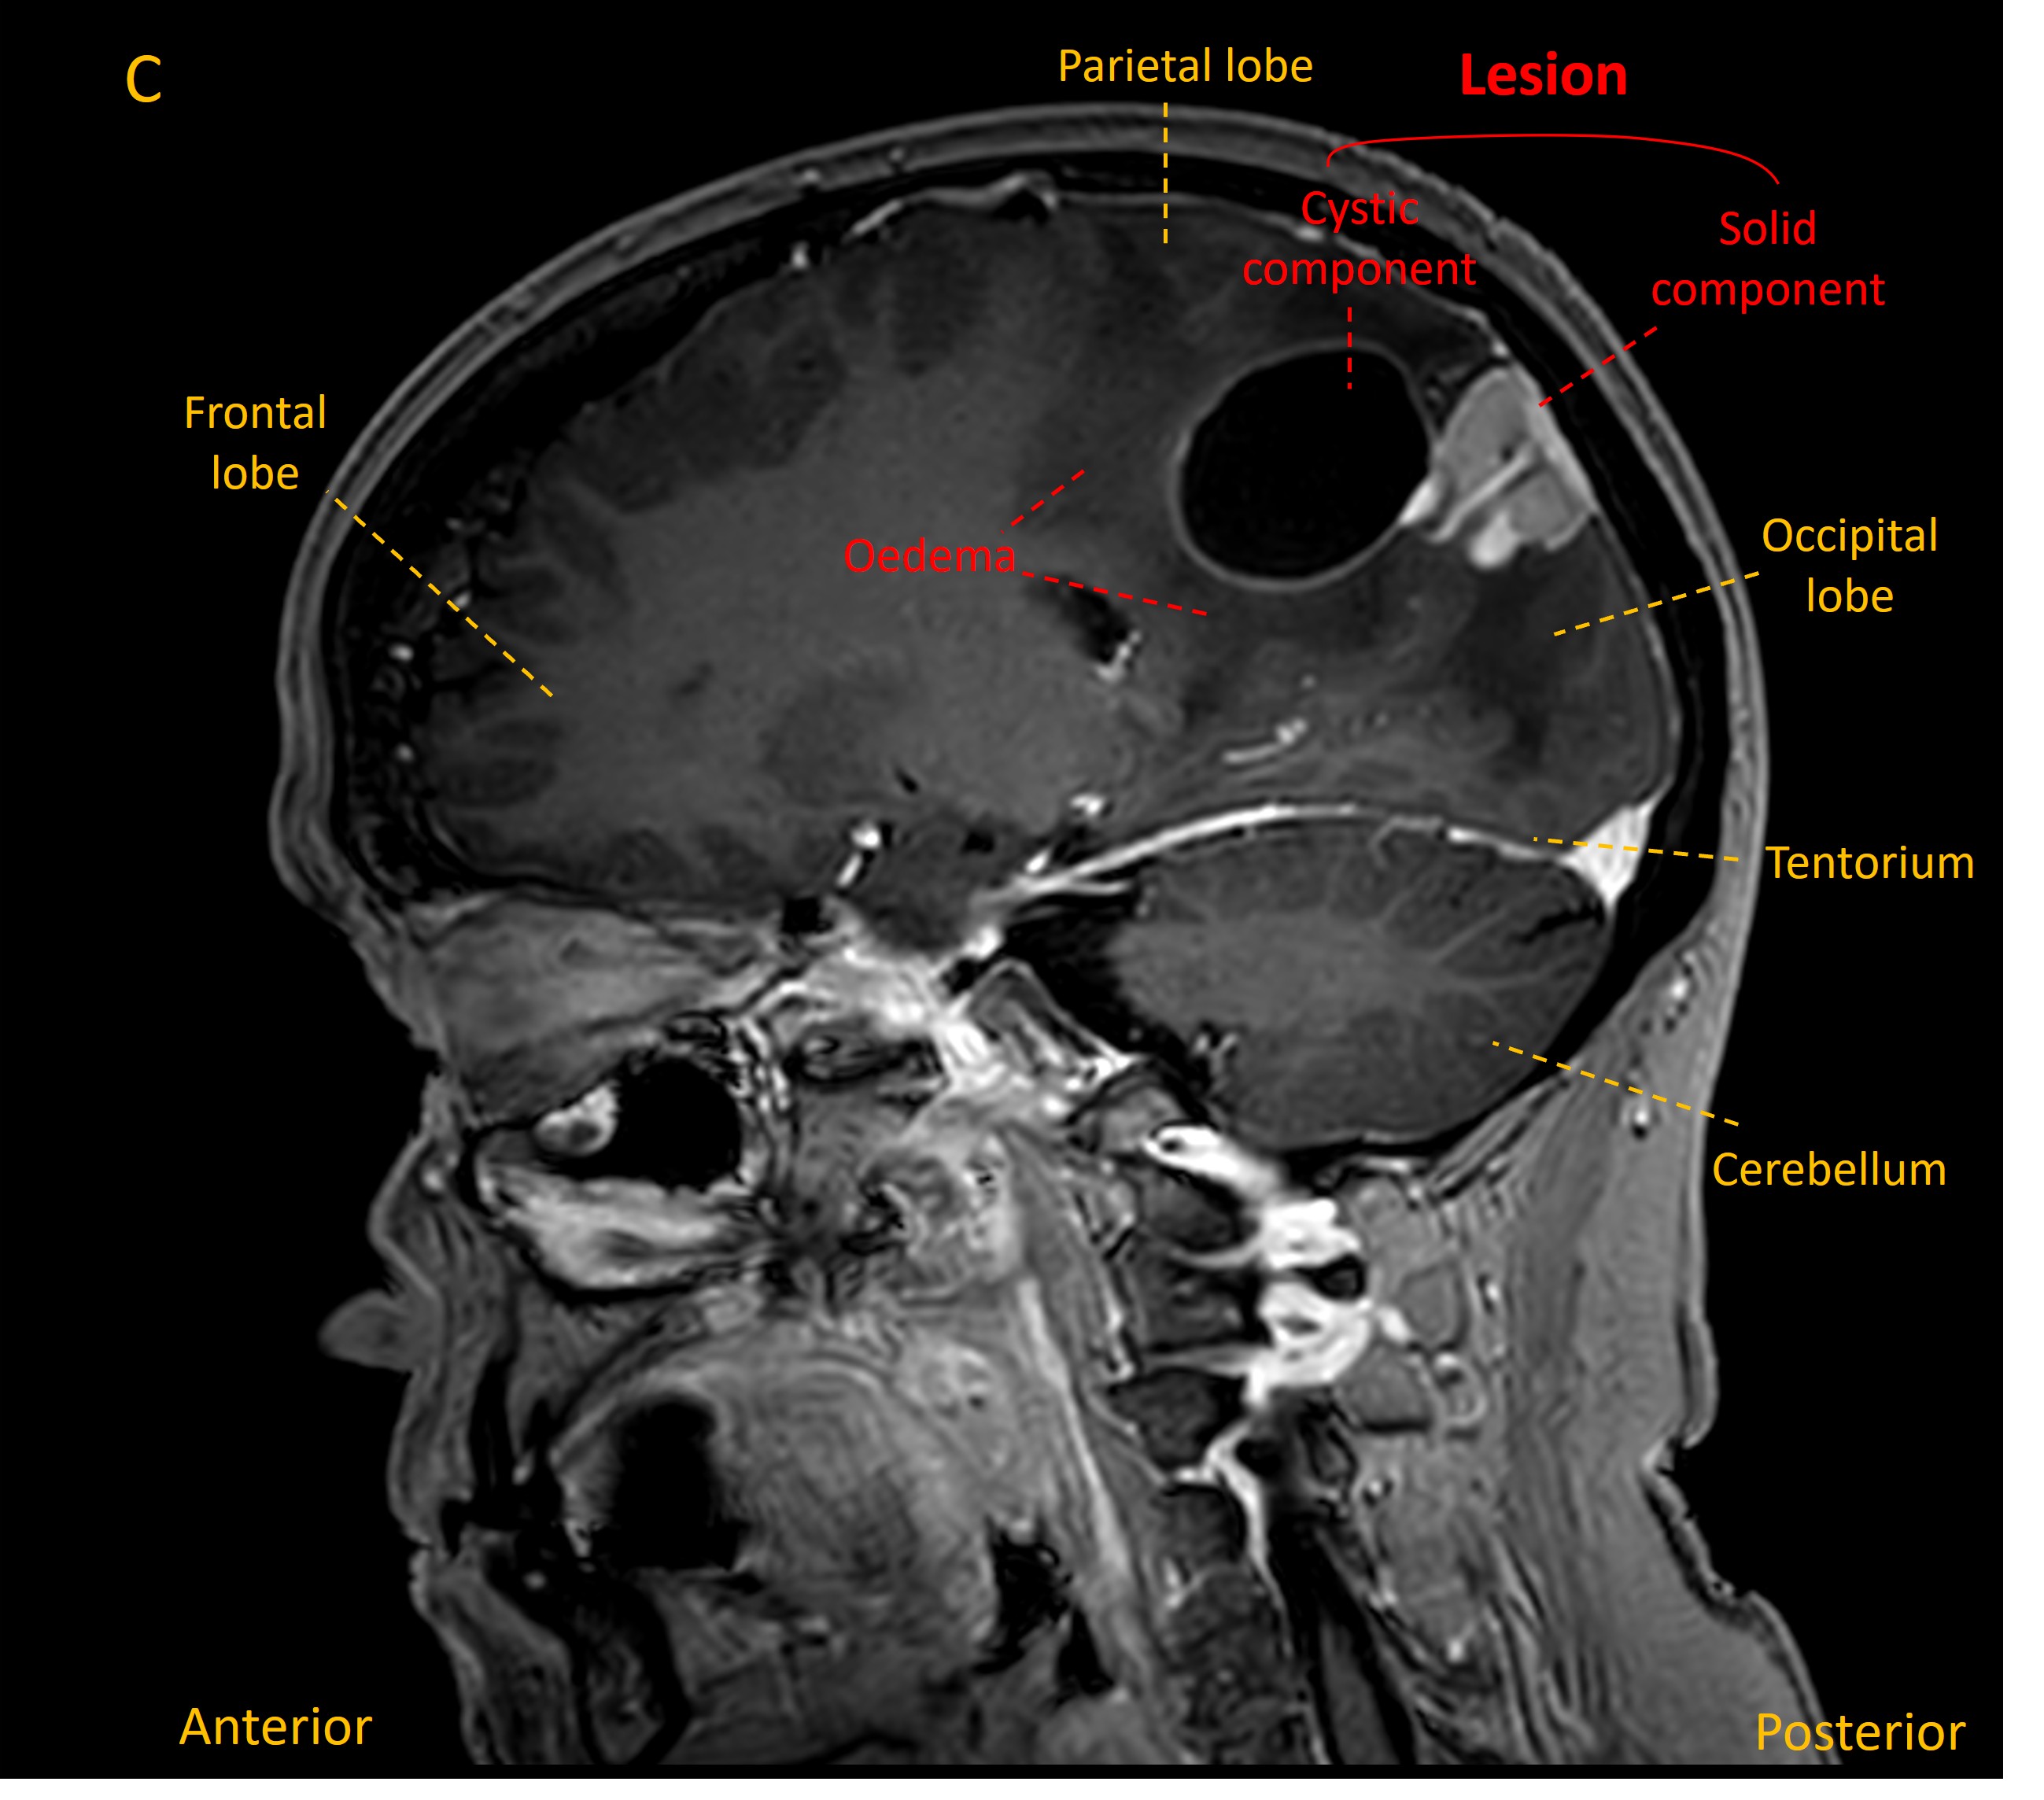

An MRI revealed a mass in the right parietal lobe with a solid component and a deeper cyst, associated with some white matter oedema and some sulcal effacement (images A-C).

MRI 1